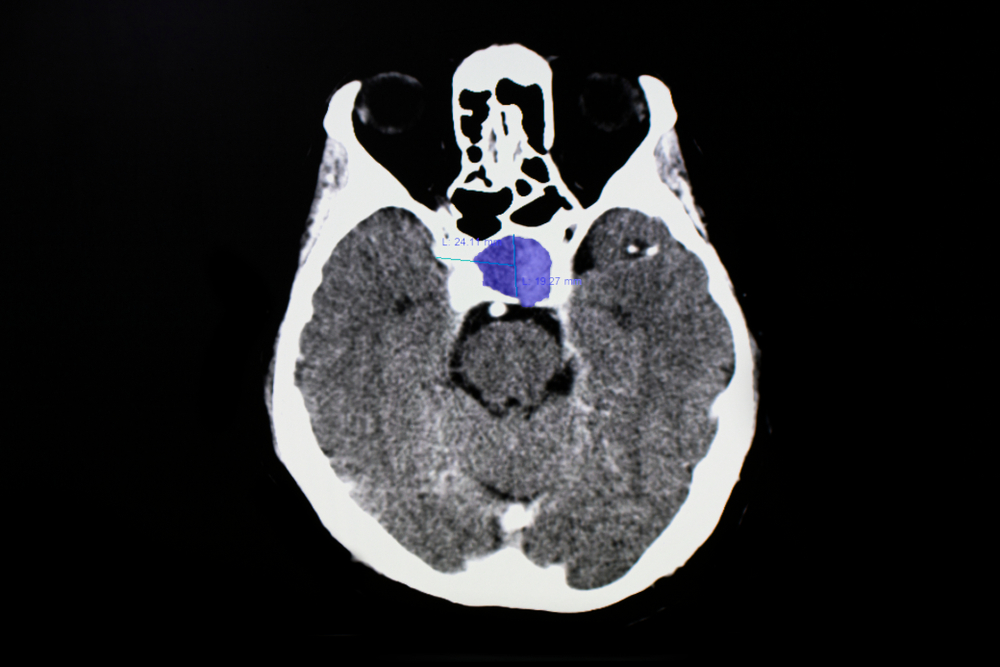

Η υπόφυση είναι ένας μικρός αλλά καθοριστικός αδένας στη βάση του εγκεφάλου, ο οποίος ρυθμίζει τις περισσότερες ορμονικές λειτουργίες του οργανισμού. Οι όγκοι της – συνήθως καλοήθη αδενώματα – μπορούν να προκαλέσουν από ανεξήγητη κόπωση και ορμονικές διαταραχές μέχρι προβλήματα όρασης και σημαντική επιδείνωση της ποιότητας ζωής. Παρότι δεν είναι κακοήθεις, απαιτούν εξειδικευμένη διαχείριση, καθώς η θέση τους είναι ευαίσθητη και η λειτουργία τους ζωτικής σημασίας.

• Σύστημα νευροπλοήγησης, που λειτουργεί σαν «GPS» του εγκεφάλου και επιτρέπει ακριβή πλοήγηση στη δύσκολη ανατομία της βάσης του κρανίου επιπροβάλλοντας ταυτόχρονα τις πληροφορίες στο χειρουργικό πεδίο παρέχοντας τη δυνατότητα στο χειρουργό να εκτελεί το χειρουργείο με τη βοήθεια εικονικής πραγματικότητας. Η τεχνική εφαρμόζεται στο κέντρο μας και για 1η φορά στην Ελλάδα από το 2006.

• Ακτινολόγοι για ακριβή προεγχειρητικό και μετεγχειρητικό έλεγχο